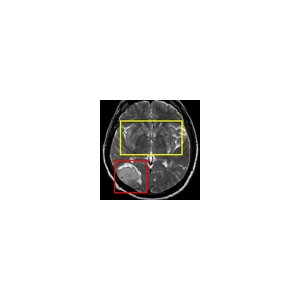

LPA - Experten aus Tirol, Trient und Südtirol befassen sich am 28. Juni in Bozen bei der Tagung „Iktus“ mit neuesten Erkenntnissen zur Vorbeugung, Diagnose und Therapie bei Schlaganfall. Die Tagung wird vom Landesamt für Krankenhäuser in der Landesabteilung Gesundheitswesen organisiert und vom EVTZ „Europaregion Tirol-Südtirol-Trentino“ unterstützt.

Bei der Tagung „Ictus", die am 28. Juni um 8.45 Uhr in der Europäischen Akademie Eurac in Bozen beginnt, setzen sich Fachleute aus den drei Ländern Tirol, Trient und Südtirol mit unterschiedlichen Fragen im Zusammenhang mit der Thematik Schlaganfall auseinander. Die neuesten Erkenntnisse zur Vorbeugung, Diagnose und Therapie stehen ebenso auf der Tagungsagenda, wie die territoriale Organisation und der Zugang zu den Leistungen, sowohl der Kardiologen, als auch der Neurologen und der Allgemeinmediziner. Bei der Tagung werden also nicht nur klinisch-wissenschaftliche, sondern auch gesundheitsökonomische, wie auch praktische Erkenntnisse für den Patienten und die betroffenen Familien aufzeigt. Organisiert wird die Tagung „Iktus" vom Landesamt für Krankenhäuser in der Landesabteilung Gesundheitswesen organisiert und vom Europäische Verbund für territoriale Zusammenarbeit (EVTZ) „Europaregion Tirol-Südtirol-Trentino".